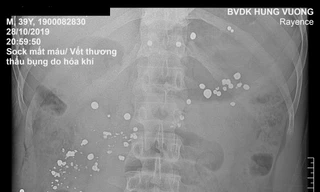

Xã hội Cành cây mục rơi vào khẩu súng, nam thanh niên bị đạn xuyên 15 lỗ trong dạ dày TPO - Bệnh viện Đa khoa Hùng Vương (xã Chí Đám, huyện Đoan Hùng, tỉnh Phú Thọ) vừa cứu sống bệnh nhân bị súng tự chế bắn thủng 15 lỗ trong dạ dày.

Sức khỏe Nam thanh niên bị súng tự chế bắn thủng 15 lỗ ở dạ dày TPO - Bệnh viện Đa khoa Hùng Vương (xã Chí Đám, huyện Đoan Hùng, tỉnh Phú Thọ) vừa cứu sống bệnh nhân bị súng tự chế bắn thủng 15 lỗ dạ dày.